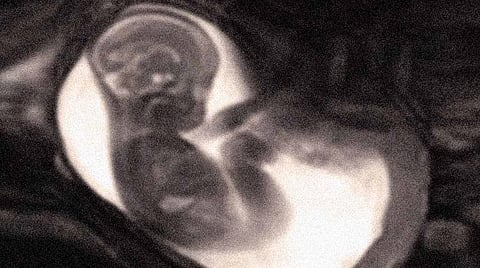

ஸ்டில்பெர்த் என்பது கருச்சிதைவிலிருந்து மாறுபட்டது. அதாவது ஒரு பெண்ணிற்கான மகப்பேறு வாரங்களான 28 வாரத்துக்கு இடையே கருப்பையில் குழந்தை இறத்தல் மற்றும் மகப்பேறு முடிந்த 36 வாரத்துக்குப்பின் மகப்பேறு காலத்தில்கூட இறத்தல் என்று குறிப்பிடலாம்.

குழந்தை பிறந்தபின்பும் அல்லது பிரசவத்தின்போதும் குழந்தை இறத்தல் என்பது குடும்பத்தில் வேதனைக்குரிய ஒன்று. ஆனால், இது உலகம் முழுவதும் தொடர்ந்து நடந்து வருகிறது. 16 வினாடிக்கு ஒரு குழந்தை கருப்பையிலேயே இறக்கிறது. ஆண்டுக்கு 20 லட்சம் குழந்தைகள் இதுபோல் இறக்கின்றன.